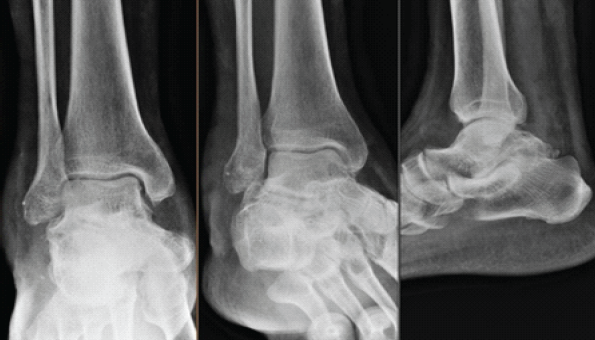

Figure 4: 1-year follow-up radiograph.